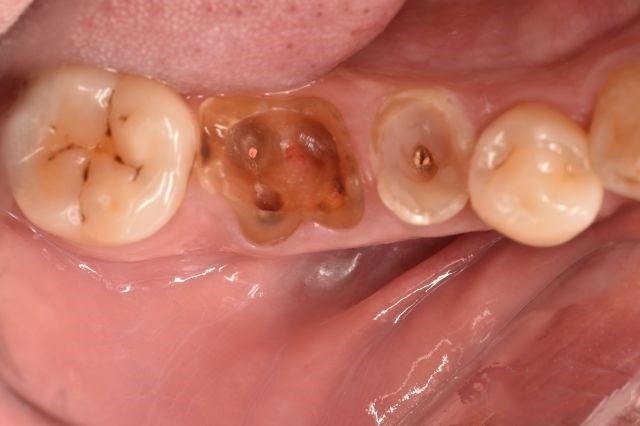

除了牙周,口腔环境对正畸的影响也很大。

成年人的口腔情况各异: 有人一口 蛀牙 ,有人 缺牙 ,有人 拔完牙留有残根 ,或是做过 假牙 等各类情况 。

如果想要正畸,得先把这些口腔问题解决才行。